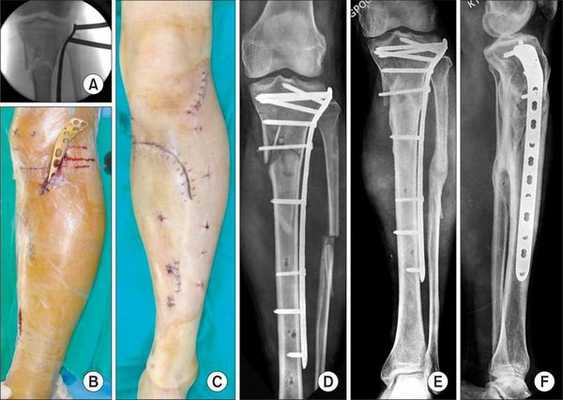

При переломах костей голени без смещения, возможности отрепонировать отломки и удержать их в правильном положении проводят скелетное вытяжение в течение 4 недель. Затем накладывают гипсовую лонгету сроком на 3-4 месяца. При невозможности сопоставить и удержать отломки, интерпозиции мягких тканей, а также для сокращения сроков лечения и ранней активизации больного врачи-травматологи применяют оперативное лечение. Используются винты, блокируемые стержни, винты и аппараты наружной фиксации.